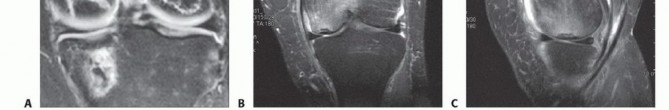

If there is no fluid tracking under the lesion on MRI, then in situ fixation is possible without any bone graft or additional reduction or curettage (

TECH FIG 2A-H

).

However, when more unstable lesions with either fluid tracking behind the fragment or free-floating fragments are encountered, these often do need bone grafting and curettage as previously described (

TECH FIG 2I-K

TECH FIG 2 • A-C. Preoperative x-ray (XR) and MRI show an OCD lesion with no fluid tracking behind the lesion. D-G. Intraoperative and postoperative images demonstrating in situ fixation with countersunk cannulated screws. H. After screw removal, postoperative imaging shows a healed OCD lesion.

TECH FIG 2 •

(continued)

I. A grossly unstable lesion with fluid tracking beneath and a sclerotic base requires aggressive removal of this sclerotic base, as it is a barrier to healing and is avascular. Local bone graft is then needed to fill the cavity created by burring and/or drilling this away. J,K. Intraoperative and postoperative images showing anatomic fixation. Screws are countersunk beneath the radiolucent cartilage surface but are slightly proud relative to the bone, giving the false appearance of not being placed deeply enough. Explaining this to families preoperatively can help avoid confusion later.